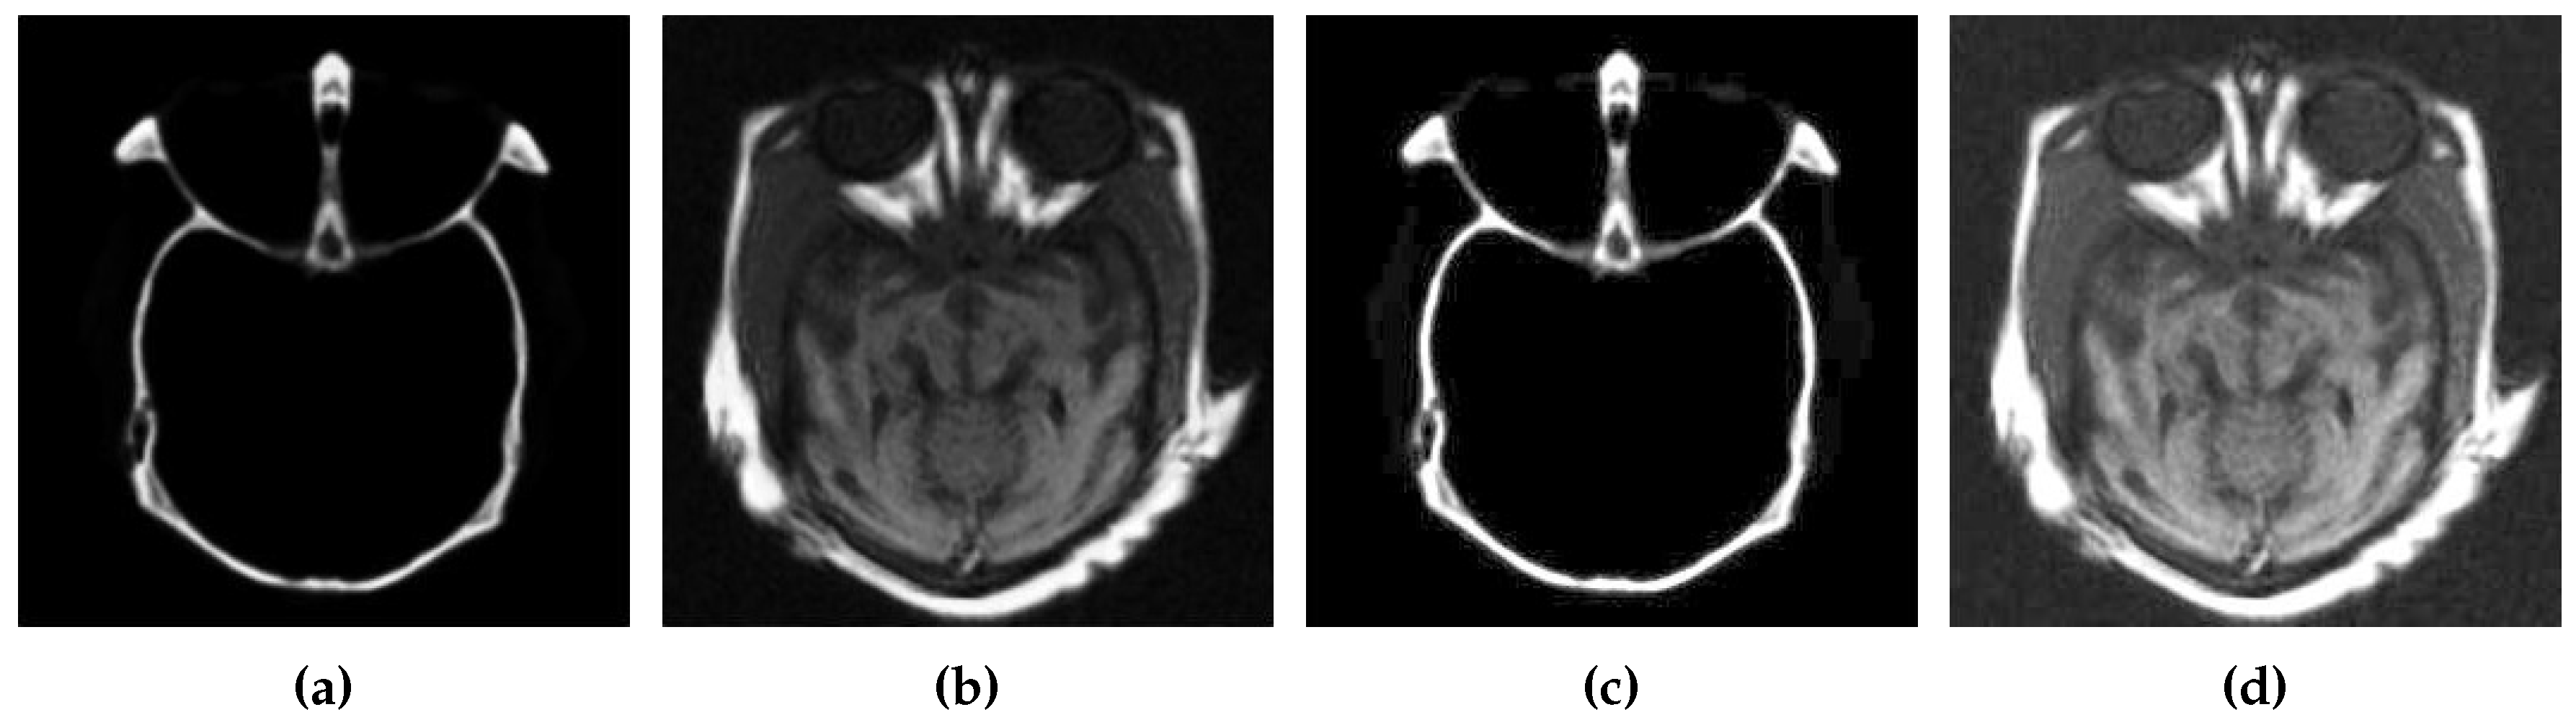

The results of contract enhancement are illustrated in Figure 2. After contrast enhancement, CSID enters the second phase, which is detailed in the following subsection.

Figure 2. Contrast enhancement results, where (a,b) represent the source images and (c,d) show images with enhanced contrast using BIMEF.